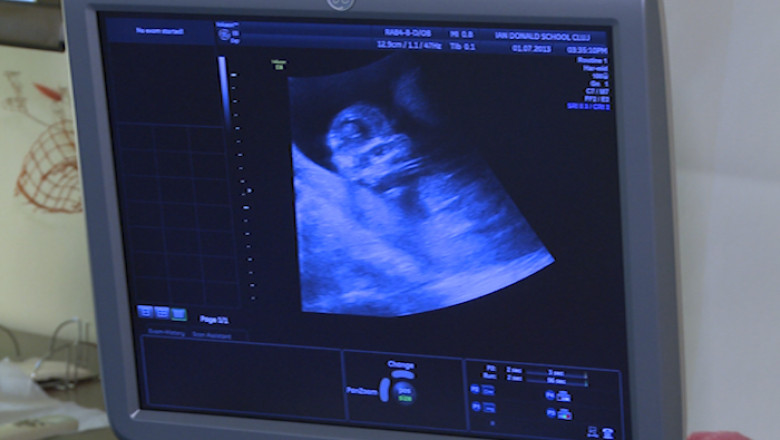

În prezent, Clinica de Obstetrică şi Ginecologie a Spitalului Municipal din Timişoara nu are aparatura necesară pentru a depista malformaţii ale fătului, astfel că mulţi copii sunt diagnosticaţi abia după naştere, când deseori este prea târziu pentru o intervenţie chirurgicală.

"Spitalul Odobescu de exemplu are unul, două ecografe care sunt departe de ceea ce vom achiziţiona prin acest proiect. În plus, prin acest proiect vom implementa şi un sistem de telemedicină prin care putem să ne consultăm, să luăm o a doua opinie în cazul unor malformaţii mai rar întâlnite", declară Olimpia Oprea, manager de proiect.